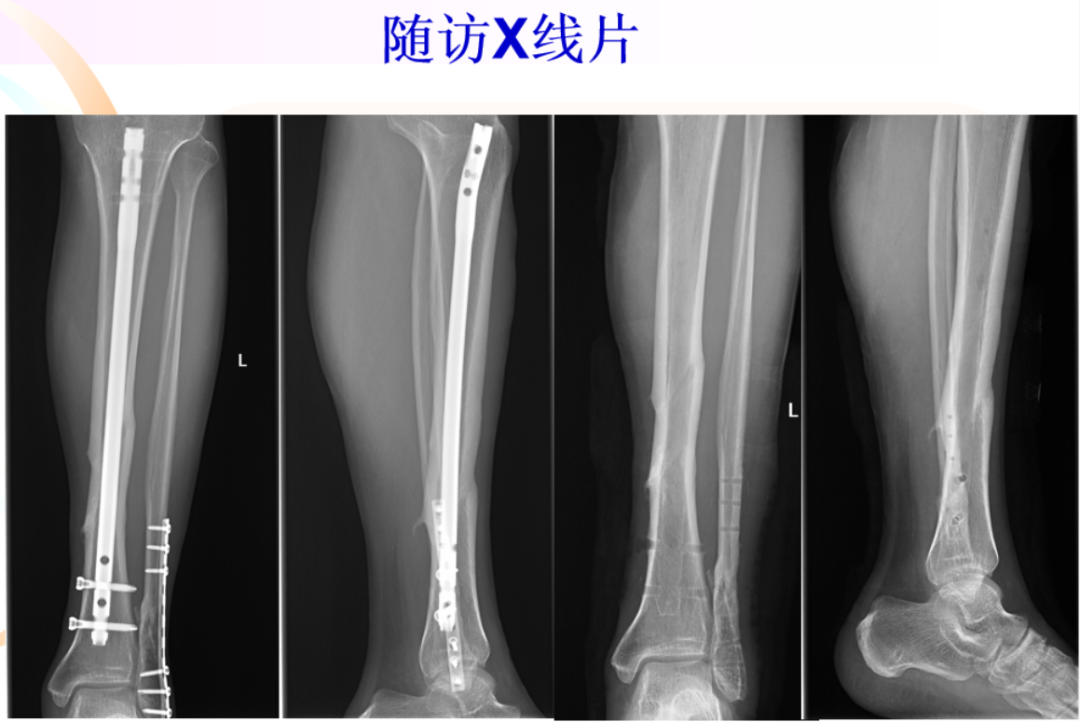

治疗:内固定?腓骨固定吗?腓骨先固定吗?下胫腓关节?术后X线片:复位顺序?复位质量?内固定选择?内固定位置?钉数与布局?预后?